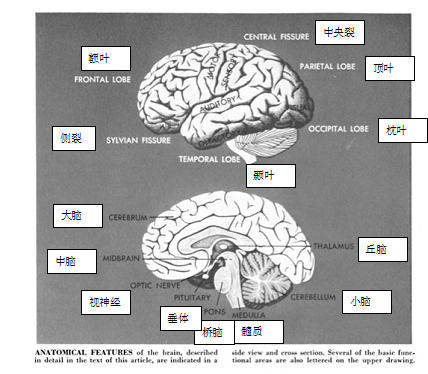

如果说过去的图片能够成为未来的向导,这并不全面。传统的大脑解剖学插图(如下图)于1948年首次出现在《美国科学人》上,当时的杂志已经开始刊登医学研究相关信息。

图片来自1948年10月《科学美国人》“巨大而凌乱的结”一文,作者:George W. Gray,插图作者:Eric Mose

数十年过去了,这样的插图依然顽强地存在着。

图片来自1979年9月《科学美国人》“大脑结构”一文,作者:Walle J. H. Nauta 和 Michael Feirtag,插图作者:Carol Donner

尽管PET扫描或MRI这样的成像技术越来越为非专业读者所熟知,并越发频繁地出现在主流媒体中,人们依然没有认为传统的解剖学插图已然过时。也就是说,为了赋予新研究更大的规模和复杂性,我们将需要努力推动具象的插图,使其更好地发展。